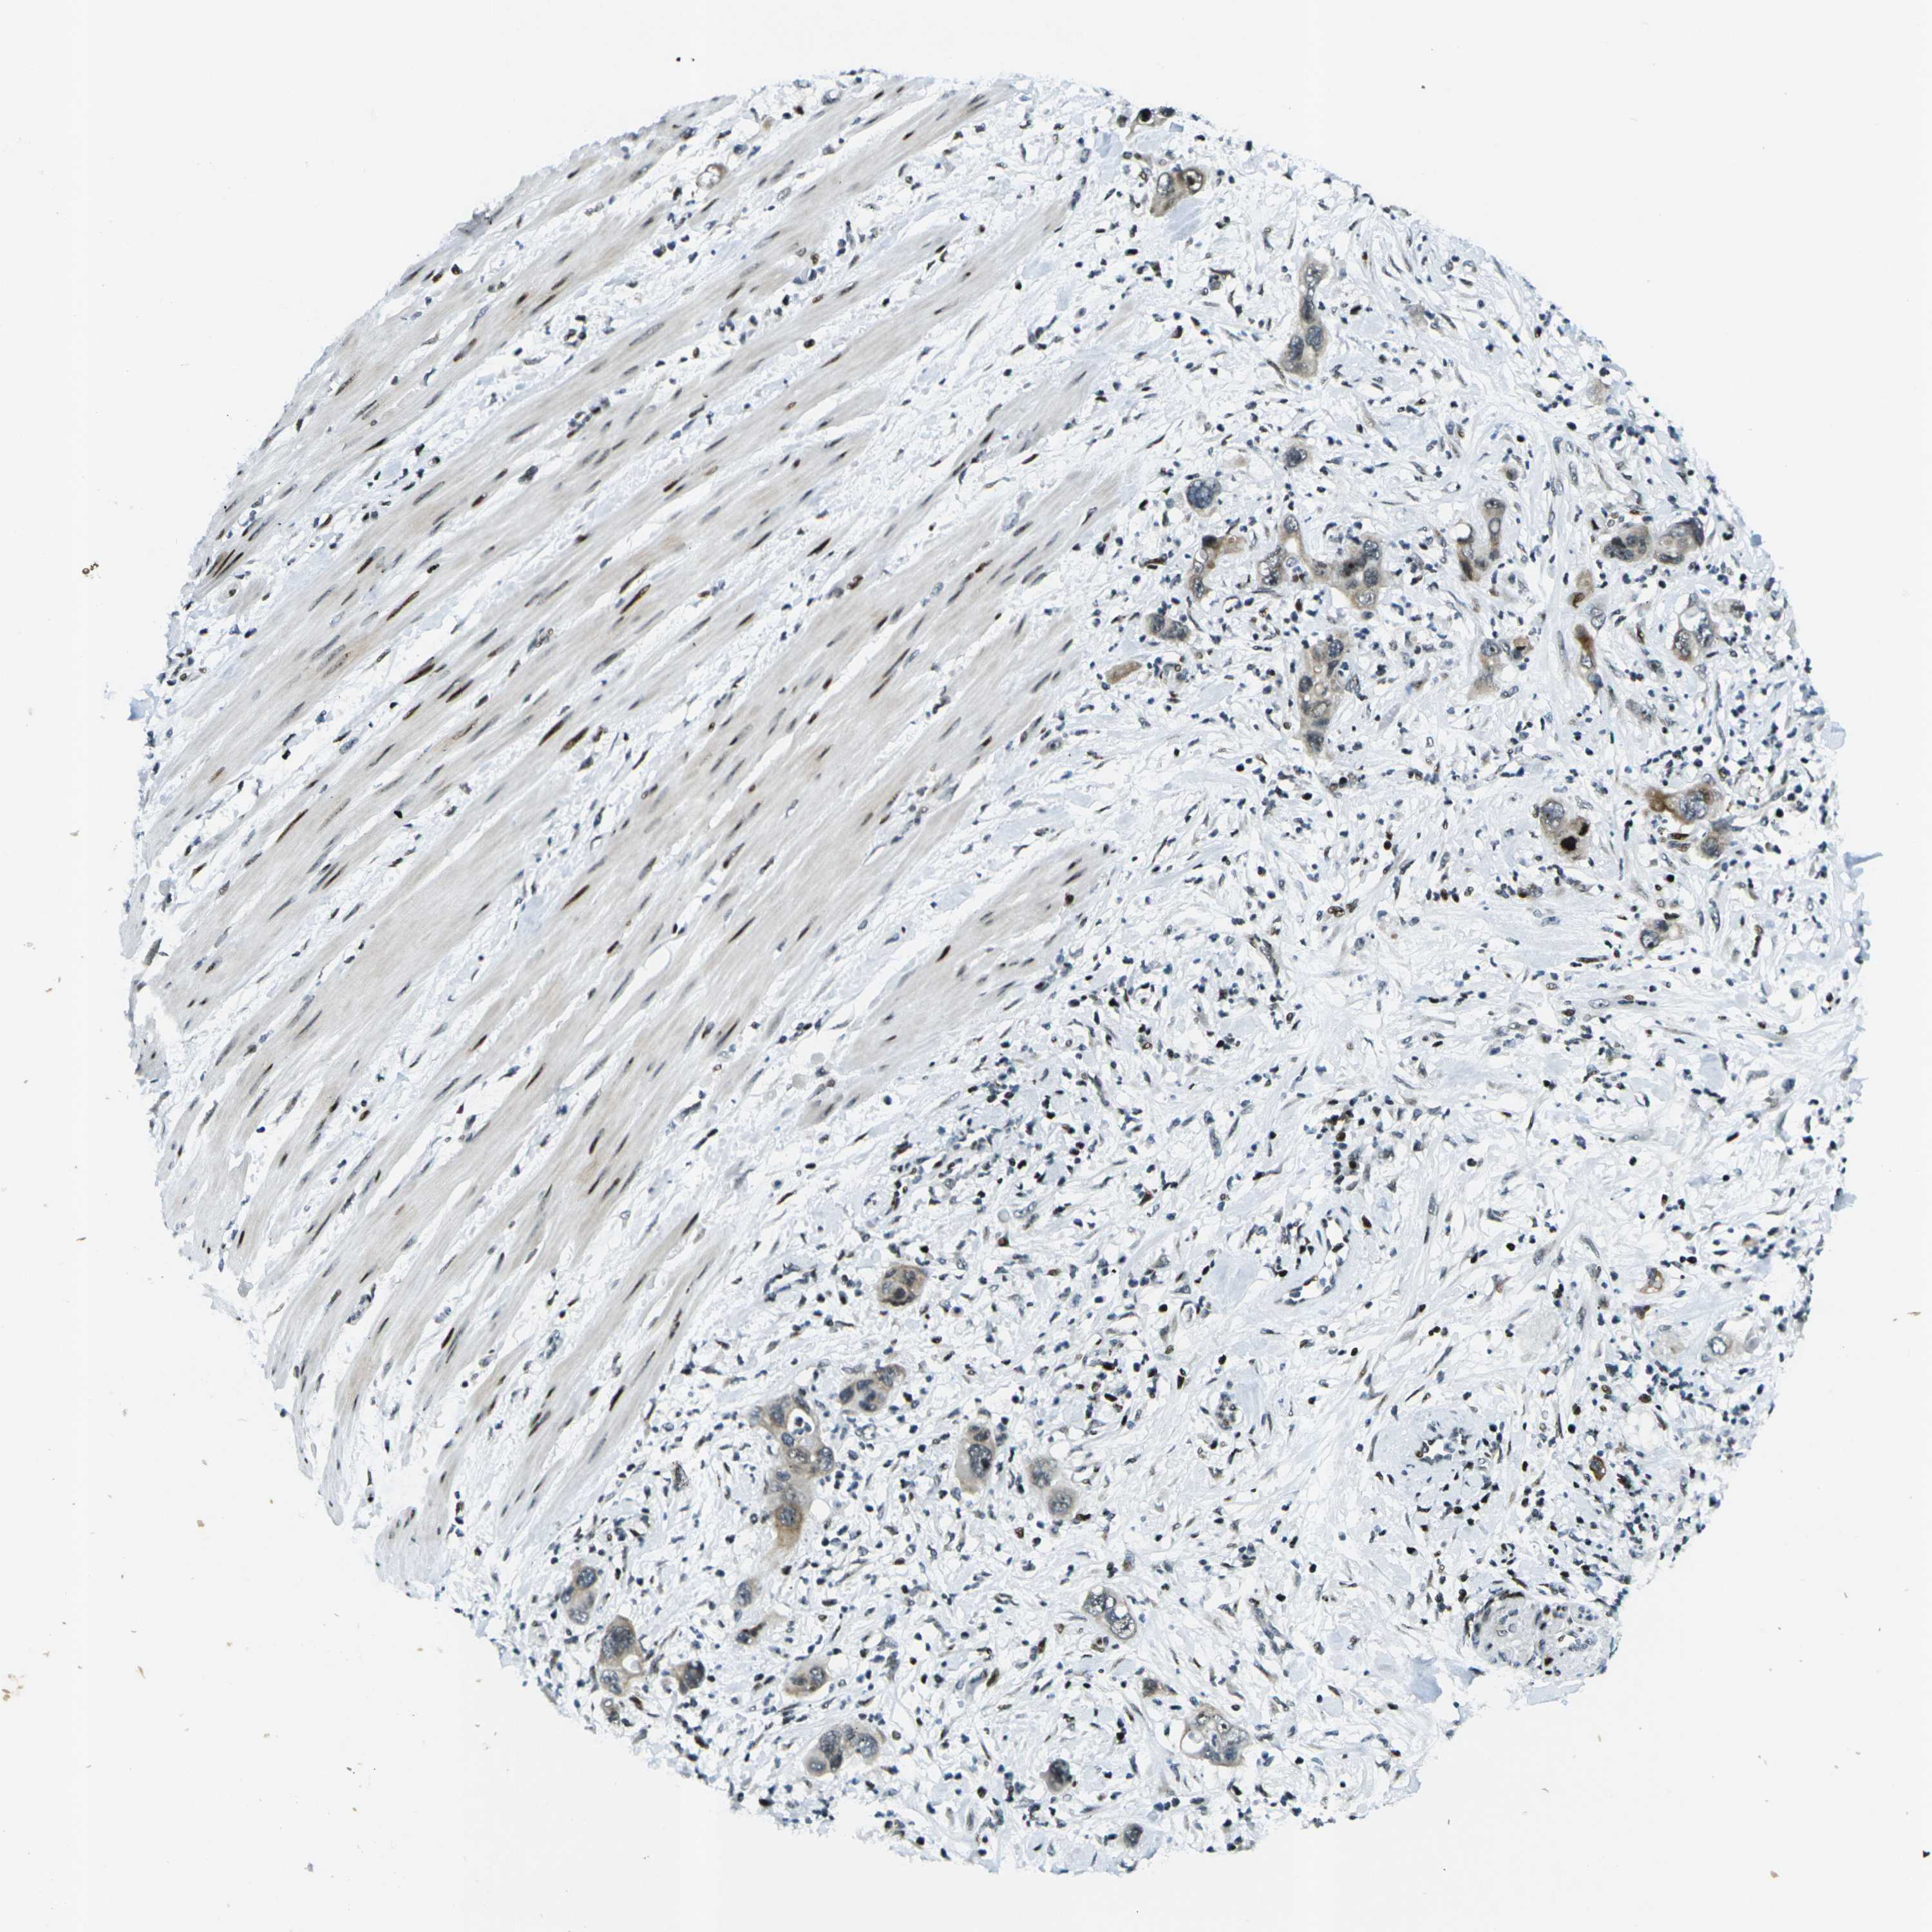

PANCREATIC CANCER - Protein expressioni

A mouse-over function shows sample information and annotation data. Click on an image to view it in a full screen mode. Samples can be filtered based on level of antibody staining by selecting one or several of the following categories: high, medium, low and not detected. The assay and annotation is described here.

Note that samples used for immunohistochemistry by the Human Protein Atlas do not correspond to samples in the TCGA dataset.

Antibody stainingi

Antibody staining in the annotated cell types in the current human tissue is reported as not detected, low, medium, or high, based on conventional immunohistochemistry profiling in selected tissues. This score is based on the combination of the staining intensity and fraction of stained cells.

Each image is clickable and will lead to virtual microscopy that enables deeper exploration of all samples and also displays staining intensity scores, fraction scores and subcellular localization as well as patient and tissue information for each sample.

Antibody CAB037178

Adenocarcinoma, NOS